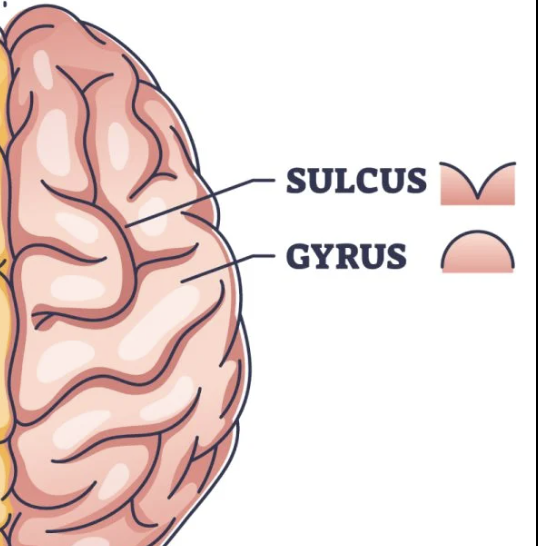

What are the ridges (folds) on the cerebrum called?

Gyrus/Gyri (Peak of the sunchip)

What are the grooves(valley) on the cerebrum called?

Sulcus/Sulci valley between the peak